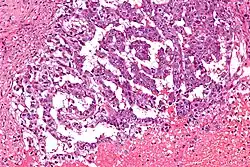

Micrograph showing the yolk sac component of a mixed germ cell tumour. H&E stain.

EST can have a multitude of morphologic patterns including: reticular, endodermal sinus-like, microcystic, papillary, solid, glandular, alveolar, polyvesicular vitelline, enteric and hepatoid.

Schiller–Duval bodies on histology are pathognomonic and seen in the context of the endodermal sinus-like pattern. Rarely, it can be found in the vagina.[6][7]